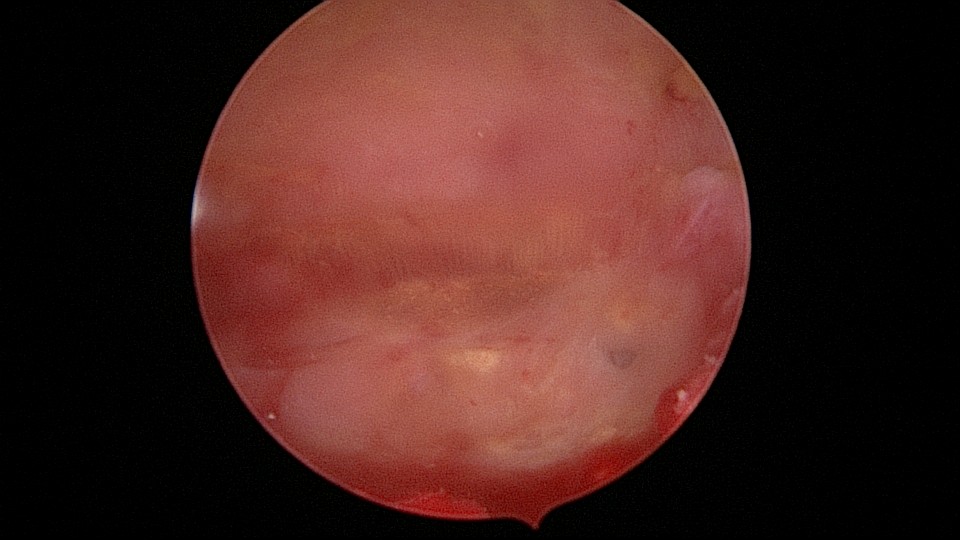

患者58岁,G2P1,顺产1次。安环35年,绝经15年,5年前在外院取环失败。术前B超提示子宫后位,O型环嵌顿,环顶端距宫底0.7cm。宫腔镜术中见阴道口狭小,无法置入窥阴器,宫颈外口狭窄,镜鞘缓慢扩大。宫颈内口粘连,左侧似有一小孔,异物钳扩大小孔,见较多浓稠黄色液体流出,冲洗干净后推进宫腔镜,见2个O型节育环,上面的环取出顺利,下面那个环与宫腔侧壁嵌顿,2次牵拉滑脱,第三次一张一驰松动节育环,再缓慢拉出,宫底见2道环压痕。